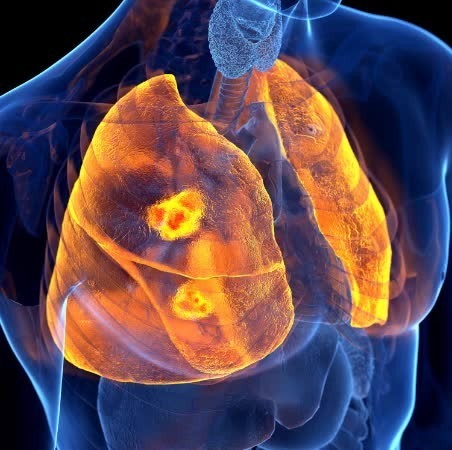

오늘은 우리 몸의 호흡을 책임지는 폐에 대해 이야기하려 합니다. 특히, 폐에 발생하는 악성 종양인 폐암의 초기 증상에 대해 자세히 알아보려 합니다.

폐암 초기증상 폐암은 초기 증상이 감기나 다른 호흡기 질환과 비슷해 간과하기 쉽습니다. 하지만 조기 발견이 치료에 매우 중요하기 때문에, 미묘한 변화라도 놓치지 않는 것이 중요합니다. 지금부터 폐암의 주요 초기 증상들을 꼼꼼히 살펴보고, 건강을 지키는 첫걸음을 함께 시작해 볼까요?

폐암 초기에는 특별한 증상이 없는 경우가 많지만, 암이 진행되면서 다양한 신호를 보낼 수 있습니다. 다음은 폐암 환자들이 흔히 경험하는 10가지 주요 초기 증상입니다.